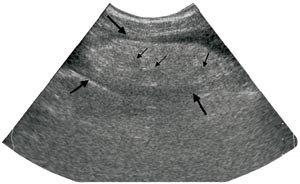

Pasient 2. En 42 år gammel mann, tidligere appendektomert og operert for etterfølgende adheranseileus, kom inn med konstante smerter i høyre nedre kvadrant av halvannet døgns varighet. Han hadde redusert matlyst, men ikke oppkast. Ved klinisk undersøkelse var han subfebril og hadde en palpabel oppfylling til høyre for umbilicus og tegn til peritonitt. Ultrasonografi viste, svarende til palpasjonsfunnet, en ekkorik, relativt homogen oppfylling med et par små sentrale hypoekkoiske foci. Den var velavgrenset fra tarm, 3 x 8 cm stor og med litt ødem omkring (fig 3). CT fremstilte i samme lokalisasjon en skarpt avgrenset lavattenuerende, inhomogen oval oppfylling med omliggende ødem. Den var 10 x 4 cm stor og hadde utseende som ødematøst fettvev (fig 4). Røntgen thorax og oversikt abdomen var upåfallende. Preoperativ diagnose var uspesifisert oppfylling eller infiltrat, sannsynligvis uten relasjon til tarm. Pasienten ble laparotomert, og det ble funnet torsjon av en del av omentet, med begynnende nekrose. Affisert fettvev ble fjernet og diagnosen verifisert ved histologisk undersøkelse.

Intraabdominalt fokalt fettinfarkt fremstilles ved CT som en velavgrenset oppfylling med fettattenuasjon av noe høyere tetthet enn normalt peritonealt fettvev (ca. -60 Hounsfield-enheter versus -120 Hounsfield-enheter) (1, 2, 6) – (9). I fettoppfyllingen ses høyattenuerende linjer eller drag arrangert i konsentrisk eller spiralaktig mønster (oftest kalt «stranding») og eventuelt mer veldefinerte foci med høyere tetthet. Dette indikerer ødem og blødning. En liten mengde fri væske nær lesjonen er hyppig til stede. Som ved ultrasonografi kan man finne fortykkelse av tarmvegg og peritoneum og masseeffekt.

Hyperattenuerende perifert sjikt omkring lesjonen er også beskrevet, men da oppfattet som å være indikator for at epiploisk appendagitt foreligger (5, 8). Vår andre pasient med omentinfarkt fremviste delvis dette tegnet på CT (fig 4), men hos ham brukte man intravenøs kontrast, som kan ha gitt oppladning i inflammert peritoneum. Andre kriterier som kan gi mulighet for å skille mellom disse to entiteter, er størrelsen og relasjonen til colon. Infarkt av oment er større enn epiploisk appendagitt, og omentinfarkt befinner seg medialt for colon ascendens eller descendens, mens epiploisk appendagitt ligger anteriørt eller anterolateralt (8). Massen ved omentinfarkt er heterogen og oftest til høyre i abdomen, mens epiploisk appendagitt er mer homogen og hyppigst på venstre side (1, 8). I praksis har det liten betydning å skille disse to former for fettinfarkt, fordi det ikke foreligger overbevisende diskriminerende kriterier og fordi symptomatologi og behandling er lik. Det samme gjelder enten det foreligger torsjon av omentet eller primært infarkt (5).